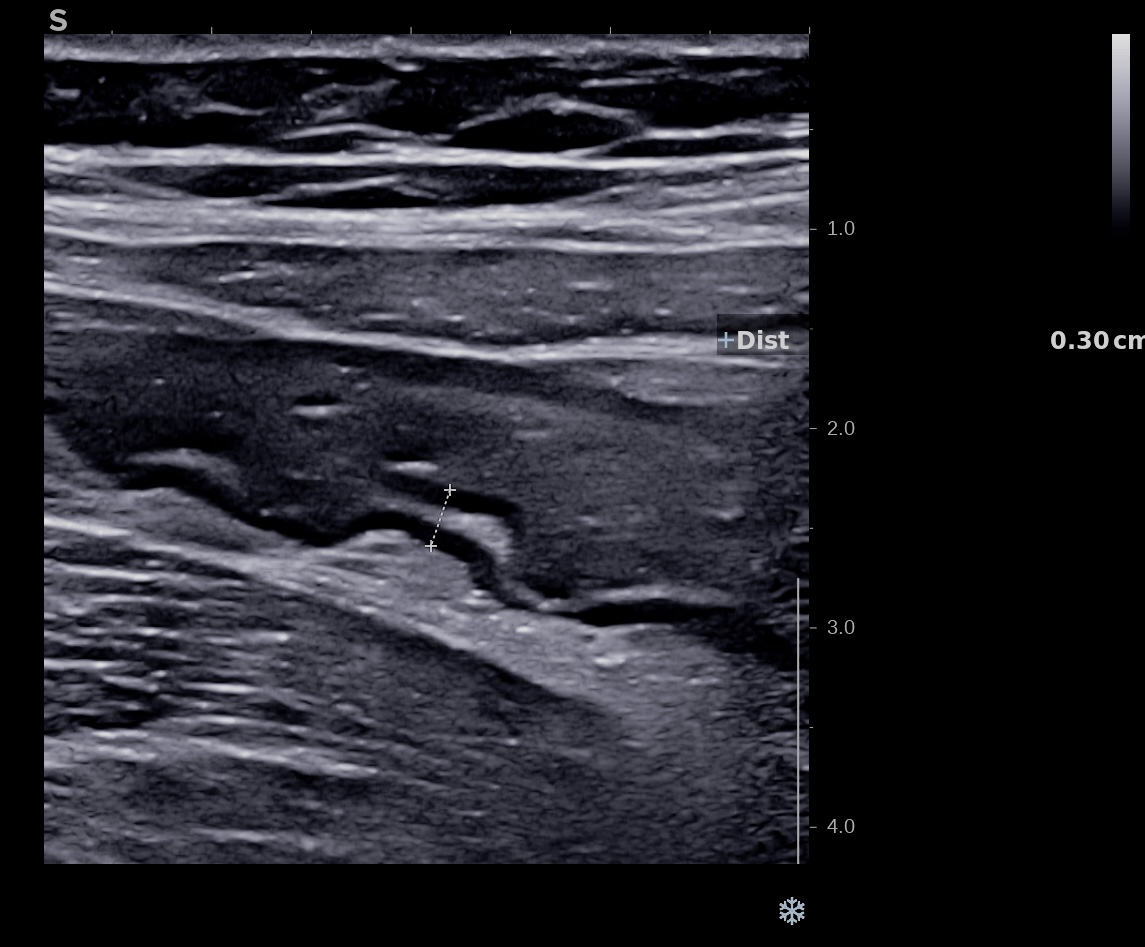

Patiente revue 4 ans plus tard sous vedolizumab Entiyo® en rémission clinique complète, biologie et calprotectine fécale normales, l’échographie (mauvaise échogénicité de la patiente) montre une paroi normalisée entre 1,8 et 2,8 mm d’épaisseur structure en couche conservée.

Le score de Milan MUC est à 3.92 confirmant la rémission échographique